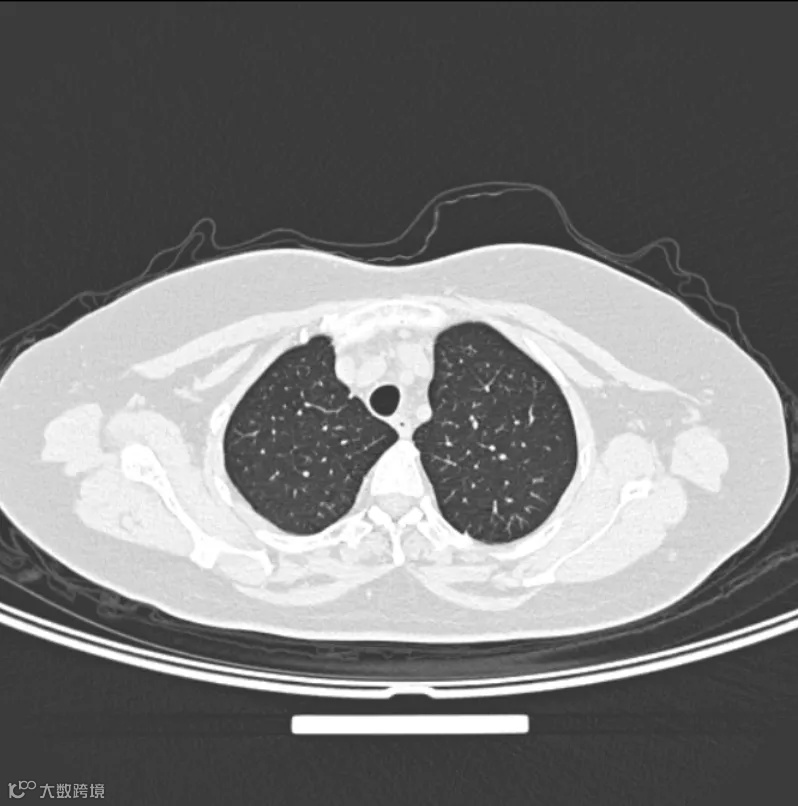

以前看CT:像看一张张切片的火腿肠,医生得自己脑补立体形状

医生以前看的CT片